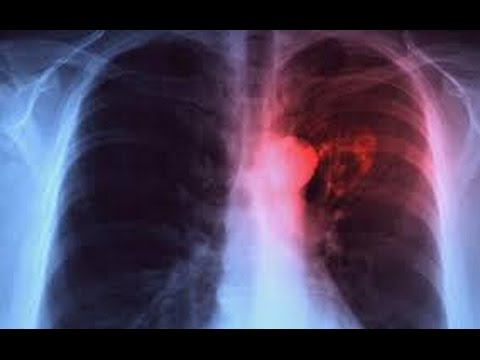

Tuberculose : Plus de 200 nouveaux cas détectés à Kaffrine

Cette maladie continue de sévir dans le pays. Kaffrine a enregistré cette année, 203 nouveaux cas de tuberculose, dont 9 décès.